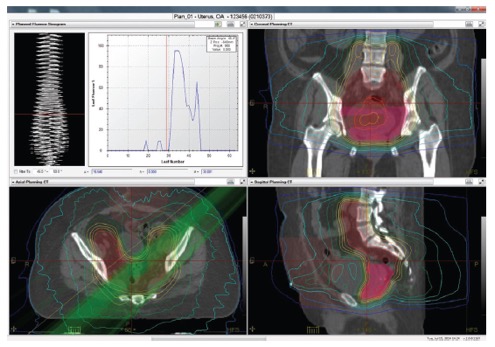

PreciseART™ - Προσαρμοζόμενη Ακτινοθεραπεία

ΔΟΣΙΜΕΤΡΙΚΗ ΠΑΡΑΚΟΛΟΥΘΗΣΗ ΘΕΡΑΠΕΙΑΣ, ΠΡΟΣΑΡΜΟΓΗ ΠΛΑΝΩΝ ΘΕΡΑΠΕΙΑΣ ΚΑΙ ΕΛΕΓΧΟΣ ΑΠΟΔΟΣΗΣ ΘΕΡΑΠΕΙΑΣ

I. Προσαρμοζόμενη ακτινοθεραπεία (Adaptive radiation therapy - ART)

- Η προσαρμοζόμενη ακτινοθεραπεία (Adaptive Radiation Therapy - ART) αποτελεί την εξέλιξη στην απεικονιστικά καθοδηγούμενη ακτινοθεραπεία για την αντιμετώπιση των ανατομικών και βιολογικών μεταβολών του ασθενούς κατά τη διάρκεια της θεραπευτικής αγωγής. Με τον τρόπο η προσαρμοζόμενη ακτινοθεραπεία παρέχει ακριβή εξατομικευμένη θεραπεία σε ασθενείς με νεοπλασίες.

II. Προσαρμοζόμενη ακτινοθεραπεία στο σύστημα TomoTherapy

Το TomoTherapy σε συνεργασία με το σύστημα σχεδιασμού Precision™ και το σύστημα διαχείρισης δεδομένων iDMS™ της εταιρείας Accuray, ενσωματώνουν όλα τα απαραίτητα εργαλεία για την εκτέλεση προσαρμοζόμενων ακτινοθεραπευτικών πρακτικών.

Το TomoTherapy σε συνεργασία με το σύστημα σχεδιασμού Precision™ και το σύστημα διαχείρισης δεδομένων iDMS™ της εταιρείας Accuray, ενσωματώνουν όλα τα απαραίτητα εργαλεία για την εκτέλεση προσαρμοζόμενων ακτινοθεραπευτικών πρακτικών.

Τα συγκεκριμένα συστήματα περιλαμβάνουν: λογισμικό για τον σχεδιασμό εξαιρετικά σύμμορφων και ομοιογενών δοσιμετρικών κατανομών, ενσωματωμένο αξονικό τομογράφο για καθημερινή λήψη εικόνων αξονικής τομογραφίας του ασθενούς, λογισμικό για την ευθυγράμμιση των καθημερινών εικόνων αξονικής τομογραφίας στις αρχικές εικόνες σχεδιασμού λαμβάνοντας υπόψη τις ανατομικές και βιολογικές μεταβολές του ασθενούς και δοσιμετρικό αλγορίθμο για τον υπολογισμό της δόσης στις καθημερινές εικόνες απεικονιστικής καθοδήγησης.

Οι ανατομικές και βιολογικές μεταβολές του ασθενούς (π.χ., απώλεια βάρους) κατά τη διάρκεια της ακτινοθεραπευτικής αγωγής λαμβάνονται υπόψη με το σύστημα PrecisesART.

Οι ανατομικές και βιολογικές μεταβολές του ασθενούς (π.χ., απώλεια βάρους) κατά τη διάρκεια της ακτινοθεραπευτικής αγωγής λαμβάνονται υπόψη με το σύστημα PrecisesART.

Το σύστημα PreciseART δίνει την δυνατότητα στους ακτινοθεραπευτές Ιατρούς να παρακολουθούν την δοσιμετρική ακρίβεια στη χορήγηση της ακτινοθεραπευτική αγωγή και να επιλέγουν πότε απαιτείται αναπροσαρμογή του πλάνου θεραπείας.

Με τον τρόπο αυτό μπορούν να χορηγήσουν θεραπείες με υψηλή ακρίβεια σε κάθε ασθενή.

PreciseART:

- Αυτόματη επεξεργασία των καθημερινών εικόνων αξονικής τομογραφίας

- Παρακολούθηση της εκτέλεσης της χορηγούμενης ακτινοθεραπείας χρησιμοποιώντας κριτήρια ελέγχου και δράσης για κάθε κλινικό πρωτόκολλο

- Εργαλεία αυτόματης αναπροσαρμογής του πλάνου θεραπείας λαμβάνοντας υπόψη τις ανατομικές και βιολογικές μεταβολές του ασθενούς κατά την διάρκεια της ακτινοθεραπείας

- Ακριβή χορήγηση της συνταγο-γραφούμενης δόσης στον όγκο στόχο προστατεύοντας παράλληλα τους υγιής ιστούς από την πρώτη έως την τελευταία συνεδρία.

III. Οι κύριες παράμετροι του συστήματος PreciseART είναι:

I. Χρήση εικόνων MVCT για την ποσοτικοποίηση της επίδρασης των ανατομικών και βιολογικών μεταβολών του ασθενούς

- Αυτόματη σύντηξη των καθημερινών εικόνων αξονικής τομογραφίας με τις αντίστοιχες εικόνες σχεδιασμού της θεραπείας του ασθενούς.

- Ενσωμάτωση στους υπολογισμούς των καθημερινών μετακινήσεων για την ακριβή τοποθέτηση του ασθενούς σε θέση θεραπείας

- Αυτόματος υπολογισμός της χορηγούμενης κατανομής δόσης στον ασθενή με βάση της καθημερινές εικόνες αξονικής τομογραφίας

II. Αυτόματη παρακολούθηση της χορηγούμενης ακτινοθεραπευτικής αγωγής

Το σύστημα περιλαμβάνει εργαλεία που επιτρέπουν στον ακτινοθεραπευτή ιατρό να παρακολουθεί την εκτέλεση της ακτινοθεραπείας και να ενημερώνεται αυτόματα για τις περιπτώσεις εκείνες που απαιτείται αναπροσαρμογή του πλάνου θεραπείας.

Το σύστημα περιλαμβάνει εργαλεία που επιτρέπουν στον ακτινοθεραπευτή ιατρό να παρακολουθεί την εκτέλεση της ακτινοθεραπείας και να ενημερώνεται αυτόματα για τις περιπτώσεις εκείνες που απαιτείται αναπροσαρμογή του πλάνου θεραπείας.

- Σύντηξη των παραμέτρων του πλάνου θεραπείας (π.χ., περιγράμματα στόχου και κρίσιμων οργάνων) με τις καθημερινές εικόνες αξονικής τομογραφίας λαμβάνοντας υπόψη τις ανατομικές και βιολογικές μεταβολές του ασθενούς

- Υπολογισμός της καθημερινά χορηγούμενης κατανομής δόσης

- Υπολογισμός της αθροιστικά χορηγούμενης δόσης

- Ενημέρωση της ηλεκτρονικής καρτέλας του ασθενούς για την δοσιμετρική ακρίβεια της χορηγούμενης ακτινοθεραπείας

- Ενημέρωση του ακτινοθεραπευτή ιατρού στην περίπτωση που ο όγκος στόχος ή τα κρίσιμα όργανα λαμβάνουν δόση εκτός των κριτηρίων ανοχής που έχει θεσπίσει.

III. Αξιολόγηση ακτινοθεραπευτικής αγωγής

Το σύστημα διαθέτει εργαλεία για την αξιολόγηση των καθημερινά χορηγούμενων κατανομών δόσης επιτρέποντας στους ιατρούς να αναγνωρίσουν πια πλάνα χρειάζονται αναπροσαρμογή.

Το σύστημα διαθέτει εργαλεία για την αξιολόγηση των καθημερινά χορηγούμενων κατανομών δόσης επιτρέποντας στους ιατρούς να αναγνωρίσουν πια πλάνα χρειάζονται αναπροσαρμογή.

- Αξιολόγηση της ευθυγράμμισης του ασθενούς σε θέση θεραπείας.

- Αξιολόγηση των ανατομικών και βιολογικών μεταβολών του ασθενούς κατά τη διάρκεια της ακτινοθεραπευτικής αγωγής

- Αξιολόγηση της καθημερινά χορηγούμενης κατανομής δόσης, της αθροιστικής δόσης μέχρι την συγκεκριμένη συνεδρία καθώς και των δοσιμετρικών διαφορών

- Αξιολόγηση της ανταπόκρισης του ασθενούς στην ακτινοθεραπευτική αγωγή.